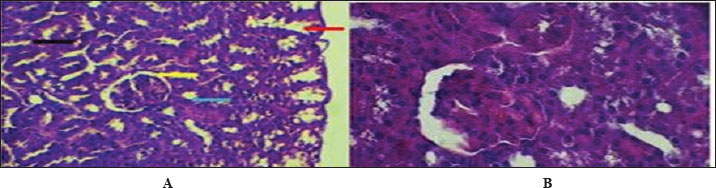

The fundamental unit of kidney structure and function presented in the Introduction was the nephron, which was a combination of the glomerulus, proximal convoluted tubule, loop of Henle, distal convoluted tubule, and collecting duct. When stained with hematoxylin and eosin, the low-power study of Fig. 1 marks off two regions in the kidney: the cortex on the outside and the medulla on the inside. The thin connective tissue capsule encompasses the cortical area on the outside of the structure (at the blue arrow). The renal cortex holds renal corpuscles and some tubules, but the interior appears mostly tubular because it consists of Henle collecting ducts and loops. One can observe renal corpuscles, which are marked by visible Bowman’s capsules, as indicated by a yellow arrow. In Figure 2, Alcian blue staining shows the renal cortex in the 40x section and proximal and distal convoluted tubules. The simple cuboidal epithelium (indicated by red arrows) on the tubules is a special feature of early postnatal development. Near the corpuscle, glomerular arterioles (blue arrows) grow to aid blood circulation. Using the Alcian stain, glycosaminoglycans located in basement membranes and the extracellular matrix are visualized, and this helps make epithelial cells more noticeable. In Figure 3, the Masson’s Trichrome-stained picture at 10x showed how the kidney’s connective tissue is organized. A thin layer (marked with the red arrow) made of fibers surrounds the organ, giving the tissue a blue-green color because of the collagen. In Figure 4, the section from the 1-week shows images of both H&E staining and Alcian blue staining of the ureter cross-sections. The ureteral lumen is small throughout and runs in the center (pictured by the red arrow). On the inside, there was a small layer of squamous epithelial cells (yellow arrows) and a thin layer of muscle envelope (blue arrows) essential for making urine flow. Alcian blue mucopolysaccharides were found in the epithelium and the space below, suggesting that the mucosa was developing at the beginning of the week. In Figure 5, two 40x showed the ureter stained with PAS and Masson’s Trichrome. The yellow arrow shows the epithelial layer, the blue arrows show circular smooth muscle fibers, and the red arrow shows the longitudinal muscle layer. The outer layer is indicated by the black arrow. The Masson stain in panel B highlights the shape and layers of the smooth muscle, where collagen fibers are shown in blue and muscle cells are shown in red to clearly display the early development of the ureter.

Fig. 1. Cross-histological section of kidneys from 1-week-old hamsters from two distinct areas: the outer cortex with a thin capsule and the inner medulla. Note renal), renal corpuscles with a thin Bowman capsule. 10x. H&E stain.

Fig. 2. Cross-histological section of cortex of 1-week-old hamsters showing the proximal and distal tubules with simple cuboidal epithelium (red arrow) and glomerulus arterioles (blue arrow). 40x. Alcian blue staining.

Fig. 3. Cross-histological section of cortex of 1-week-old hamsters showing the proximal and distal tubules with simple cuboidal epithelium (red arrow) and glomerulus arterioles (blue arrow). 40x. Alcian blue staining.

Fig. 4. Cross-histochemical section of the ureter in hamsters aged 1 week showing a narrow lumen (red arrow) in the middle, simple squamous epithelial (yellow arrow), and thin smooth muscle (blue arrow). A- 10x. H&E stain. B- 20x Alcian. blue.

Fig. 5. Cross-histological section of the ureter in hamsters aged 1 week. Simple squamous epithelial (yellow arrow), thin smooth muscle circular (blue arrow), and longitudinal (red arrow) with serosa (black arrow). 40x A-PAS, B- 40x. mason trichrome.